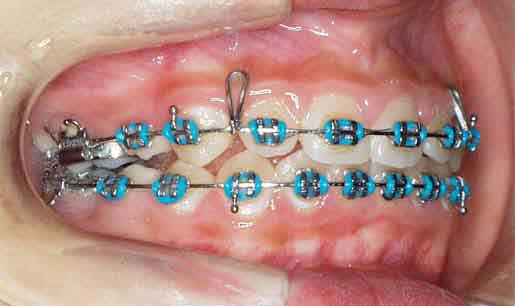

治療開始6ヶ月